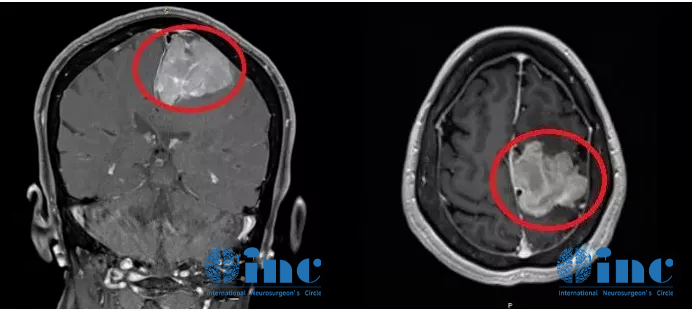

家人辗转求医最终找到INC德国巴特朗菲教授,王女士的治疗才迎来转机。在教授所在的德国INI国际神经学研究所、由INC德国巴特朗菲教授主刀的一场高质量手术直接全部切除了患者大脑深部复杂部位的脑膜瘤,她大脑中的“定时炸弹”被彻底摘除。如今手术已过去了1年半,从其术前MR、刚手术后的MR、术后1年半多的MR可以清楚看到未见复发迹象,患者现在一切生活如常,幸福的晚年生活不必再被可怕的肿瘤打扰。

术后一年半MR

脑膜瘤的预后情况、并发症的发生率及恢复时间与肿瘤位置、生长特点、术者的技术经验等息息相关,对于解剖位置比较复杂的脑膜瘤,例如枕骨大孔区、斜坡位置深,风险高,可操作空间狭窄,切除肿瘤必须跨过很多神经,容易损伤神经及脑干。手术难度大,导致切除不干净,如果强行切除,神经损伤引起瘫痪等副作用的风险就急剧升高。

例如此病例,大脑镰和矢状窦的脑膜瘤经常侵犯重要大血管甚至存在严重黏连,导致肿瘤不易全切或者容易伤及大血管,造成严重的神经损伤,这样因为肿瘤侵及矢状窦容易出血,切除这血管上的肿瘤难度高、风险大。因为它们会影响手术的可及性并确定是否可以完全切除,并保证患者正常的神经功能不受损伤。而寻找世界知名神经外科专家的手术治疗,为的就是对于高难度手术的高切除率、低风险、低副作用,而且脑膜瘤如果第一次手术能够安全全切,那么复发的可能性就越低,无进展生存期(PFS)就越长,总体预后(Prognosis)和总生存期(OS)就越好,避免术后神经功能损伤、恢复不佳的经济及社会心理负担等,生活质量更大程度地得到保障。